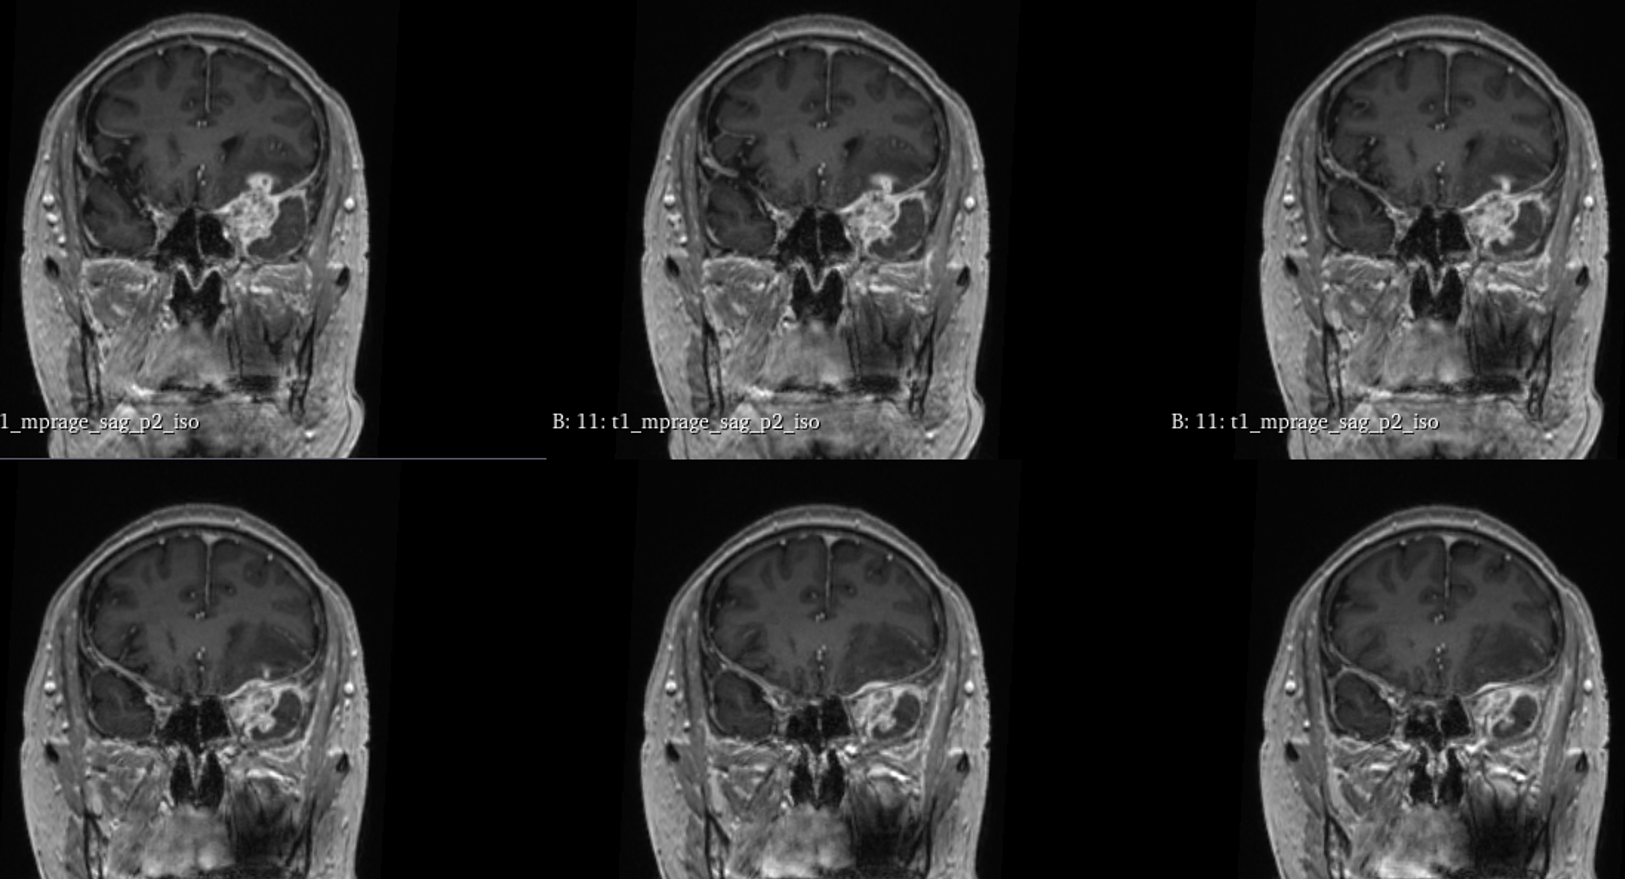

该患者入院后完善常规颅脑影像学检查,左侧颞叶病变,疾病性质不详,转移瘤、胶质瘤、炎症类疾病均不能排除,遂行PET-CT检查,提示左侧颞叶高代谢,淋巴瘤不能排除。组织MDT会诊建议可先行腰椎穿刺查脑脊液脱落细胞学、感染指标,若仍不能确诊,可进一步行开颅病灶切除,术中快速冰冻,根据冰冻结果决定手术手术策略。患者脑脊液脱落细胞学结果:较多淋巴细胞,少许单核细胞及个别中性粒细胞,未见异形细胞,脑脊液常规、生化、脑脊液培养未见细菌生长,诊断仍不能明确,且患者病情进展迅速,患者神志呈昏睡状态,颅脑MRI提示病变较前明显增大(影像学检查间隔两周),且水肿明显加重,遂行开颅病变切除术。术中见部分病变累及蝶骨嵴硬膜,病变质地硬韧,内有多个囊腔,囊内容物为黄色粘稠样脓性物质,留取囊液及实性部分送快速冰冻,在等待冰冻过程中,进一步探查见肿瘤侵犯左侧颞叶,该部位肿瘤质地相对软,无包膜,与周围脑组织无边界,血运不丰富,内有多个囊腔,且肿瘤侵犯侧裂池、颈动脉池,左侧视神经、颈内动脉、大脑中动脉均被病变包绕,且该处肿瘤质地偏硬韧。术中快速冰冻提示组织大片变性坏死,伴胶质增生及淋巴增生。结合病变质地及冰冻结果,考虑为非肿瘤性疾病,可能为炎性病变伴肉芽肿形成可能性大,且肿瘤质地硬韧,累及范围广泛,难以全切,遂行肿瘤大部分切除后结束手术。术后病理结果明确后予以伏立康唑、醋酸卡泊芬净抗真菌治疗。在治疗过程中患者先后出现脑出血、脑梗塞,最终因治疗周期长,花费高、效果不确定等因素,家属放弃治疗,于术后1月去世。

颅内曲霉菌病(intracranial aspergillosis,ICA),又称中枢神经系统曲霉菌病,是一种由曲霉菌侵袭感染脑实质、脑膜(硬脑膜为主)、脑血管及海绵窦等颅底结构引起的侵袭性真菌病。ICA由Oppe首次报道于1897年,该病临床少见,但随着激素、免疫抑制剂及广谱抗生素的广泛应用,其发病率逐年上升。ICA的临床及影像学表现缺乏特异性,核心症状异质性大,诊断及鉴别诊断困难。ICA占颅内真菌感染的5%-10%,占侵袭性曲霉菌感染的14%-42%,ICA更易累及男性,男女比例为2.25∶1。曲霉菌在自然界中广泛存在,是一种机会致病菌。其分生孢子可经呼吸道进入人体,定植于肺部、鼻窦等空腔内。当机体免疫力降低时,曲霉菌在组织、器官或血液中生长、繁殖,导致炎性反应及组织损伤,可经两种途径即局部浸润及血行播散侵入颅内导致ICA。据报道,18.0%-66.7%的患者由鼻窦、中耳及乳突中的曲霉菌感染浸润引起(窦源性ICA),该患者合并慢性鼻窦炎,考虑为窦源性。ICA可累及脑血管、脑实质、脑膜(硬脑膜为主)及颅底结构,导致坏死、化脓及慢性肉芽肿。曲霉菌侵及脑血管后,既可因菌丝填充或炎性反应导致脑梗死,又可因曲霉菌性动脉瘤破裂导致脑出血或蛛网膜下腔出血。该病多呈急性或亚急性起病,进行性加重,临床表现多样且缺乏特异性。

GM实验,GM是曲霉菌细胞壁的主要成分,是疾病早期释放至体液中的抗原之一。据报道,脑脊液GM试验诊断ICA的敏感度及特异度分别为88.2%及96.3%,且阳性预测值及阴性预测值均超过90%,脑脊液GM水平与曲霉菌感染严重程度相关,监测该指标可评价治疗效果及预后。影像学检查具有多样性,多为反复慢性炎症、肉芽肿样改变,部分易累及颅底。

目前确诊ICA仍依赖于病灶切除或活检,获得组织病理学、直接镜检或培养证据。《颅内曲霉菌病诊治中国专家共识》推荐:当临床症状怀疑ICA时,应尽早行脑脊液检查(常规、生化、培养、G试验、GM试验及mNGS)及颅脑MRI平扫+增强检查。怀疑窦源性ICA时,还应加做颅底CT检查。当临床症状符合ICA,但上述检查结果为阴性时,可重复送检。条件允许时,及时行标本镜检与培养获得确切证据。尤其是对于长期应用激素、免疫功能缺陷高危患者。